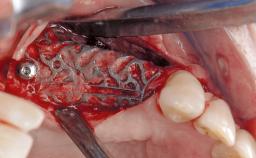

Late Presentation of Peri-Implant Mucositis Requiring Soft-Tissue Augmentation and Esthetic Crown Lengthening at Implant Site 11

Eduardo R Lorenzana, Jason R Gillespie

Biological or technical complications around implant-supported prostheses place a significant burden on patients as well as the surgical and restorative team. Inflammation of the peri-implant soft tissues is often the first sign that something has gone awry. While there is never a good time for a complication, late presentation of inflammation in the soft tissues around a long-standing prosthesis triggers a period of research and review of the case in order to ascertain the treatment history and its possible contribution to the etiology of the situation. This becomes more complicated in situations where a patient has not received regular maintenance and clinical/radiographical examinations due to personal, financial, or professional reasons. When the complication occurs in the esthetic zone, the complexity of the situation expands exponentially, as the only acceptable outcome in the patient’s eyes will be the maintenance of the esthetics of the prosthesis.